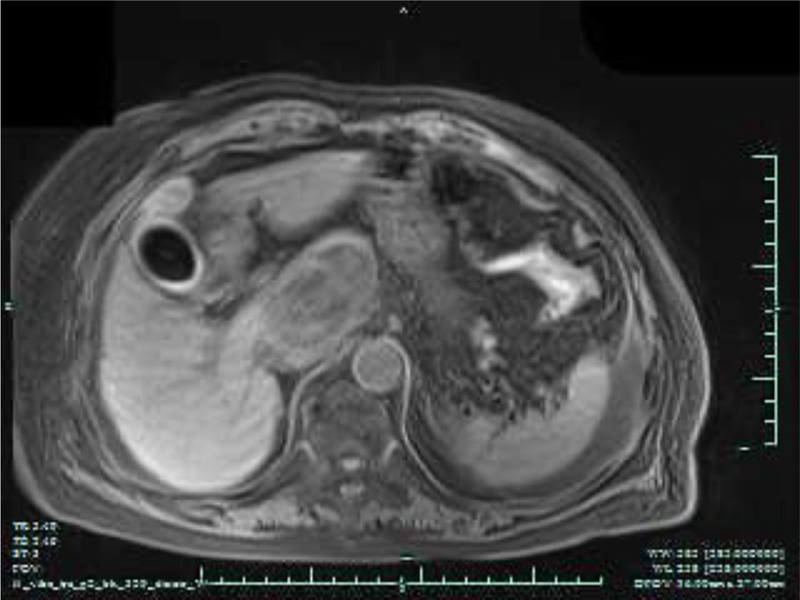

EUS-guided drainage of multidrug-resistant enterococcal caudate lobe abscess inaccessible with percutaneous approach (with video).